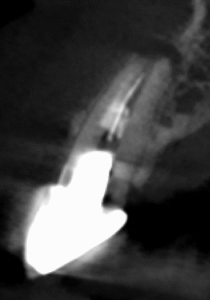

この後、作業長を測定するのだが

K Fileの#70で穿通した。

この画像ならそれも致し方ないのかもしれない。

しかし、臨床的に重要なことは、

再根管形成はもう不可能である

ということがわかる。

残された手段は…洗浄だ。